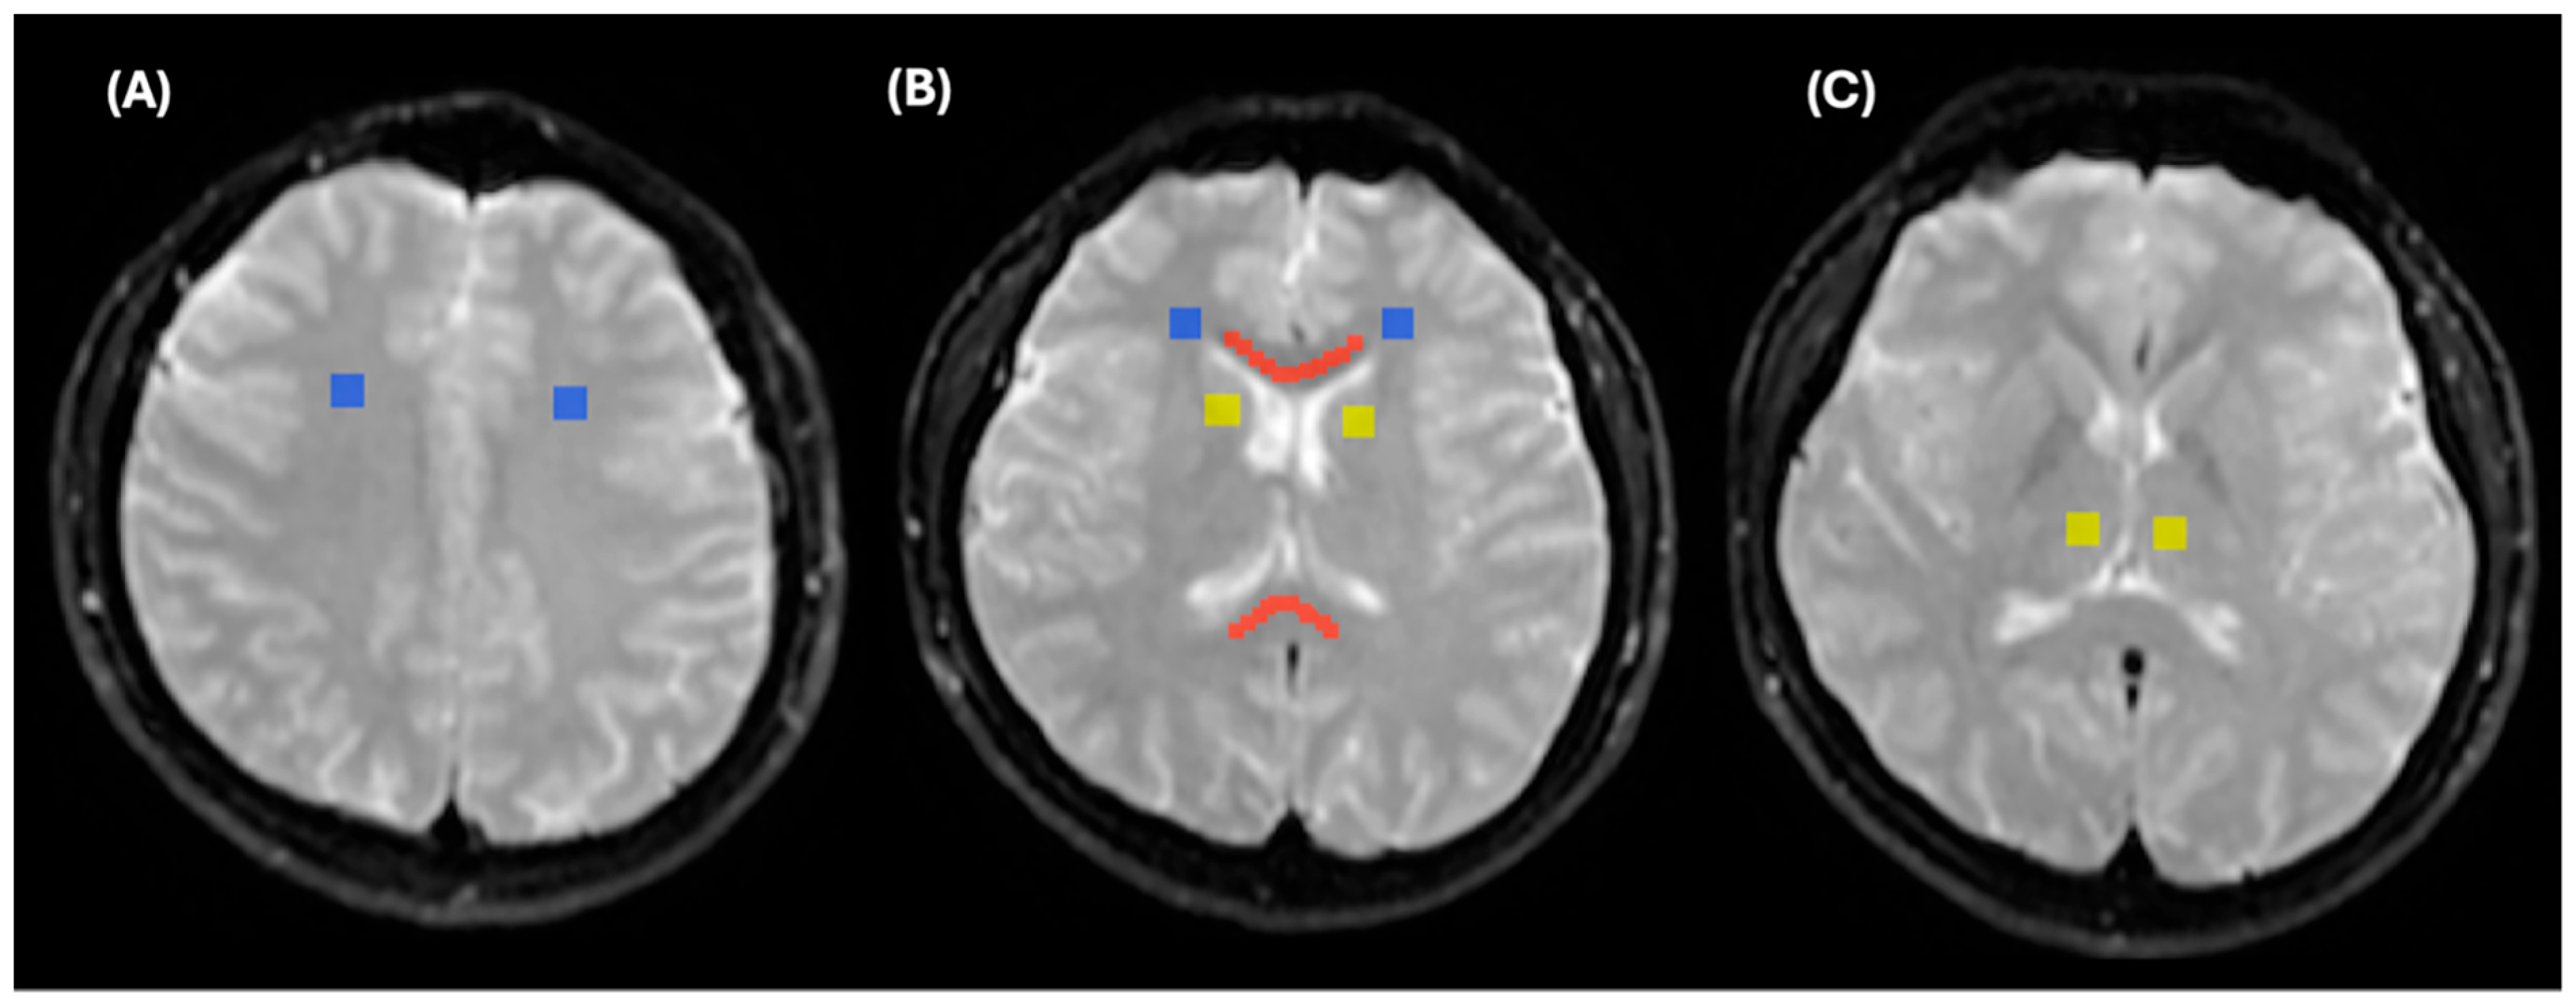

A similar registration approach was utilized for both control subjects and MS patients. However, for control subjects, we used b0 as a reference image because 2D T1WI and T2WI were not acquired for healthy participants. Figure 4 demonstrates the registration of b0 to all IVIM parametric maps.

Linear registration FLIRT FSL helped to limit rotation, scaling, shearing, and translation, which might occur due to patient movement or image distortion. This registration method was appropriate because all images were registered within the same subject. This in turn improved the experiment’s workflow and ROI selection in the same 2D structural images and 2D IVIM parametric maps for both control and MS patients. This consequently allowed us to quantify ADC, D, D*, and f values using the IVIM parametric maps in both control and MS patients by reading out all ROIs using ITK-SNAP [39], as shown in Figure 5 and Figure 6.

Regions of interest (ROIs) for control participants were delineated using b0 images with the ITK-SNAP program [39]. Four ROIs were outlined for control participants, including the genu of the corpus callosum (GCC) and the splenium of the corpus callosum (SCC), both marked in red; the white matter, marked in blue; and the deep white matter, marked in yellow, as shown in Figure 5. Measurements from the GCC and SCC were averaged and collectively referred to as the corpus callosum (CC). Similarly, measurements from the right and left frontal white matter areas, as well as the right and left frontoparietal white matter at the convexity, were averaged and collectively referred to as the WM. Measurements from the right and left thalamus and the right and left caudate nuclei were averaged and collectively referred to as the deep white matter. The size of CC ROIs was maintained at 600 ± 50 mm2, while the sizes of the white matter and deep white matter ROIs were maintained at 284 ± 5 mm2.

Figure 5. Regions of interest (ROIs) for control participants, delineated on b0 images using ITK-SNAP. (A) WM (blue colour), (B) SCC and GCC (red colour), (C) deep WM (yellow colour).